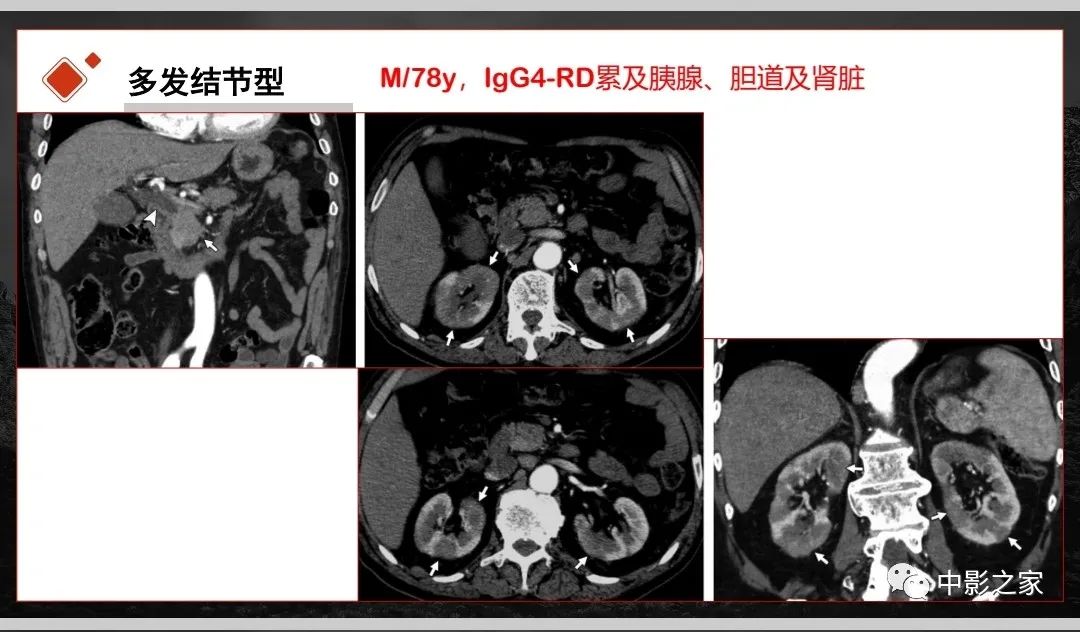

肾脏IgG4-RD临床、病理及影像特征